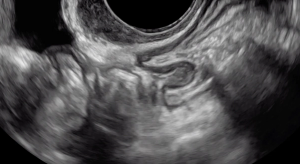

The beginning of the clip depicts a thin hyperechoic layer just deep to the vagina, which represents the rectouterine pouch peritoneum.

Following the hypoechoic layer of the bowel wall throughout the clip, viewers can appreciate the consistency of the thickness and echogenicity of this layer.